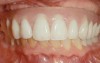

Fig 13. An All-on-4 approach was used to treat both arches with interim immediate and eventual definitive restorations.

Figure 13

Fig 14. Final restorations used for 6-1/2 additional years.

Figure 14

This is an unfortunate mindset in that current advances in protocol and technology can result in significant advantages in addressing some or most of these concerns. The patient shown in Figure 12 may serve to illustrate this point. She had a destroyed maxillary dentition, a less-compromised but highly unesthetic mandibular component, and a single goal: to be able to "smile at my grandchildren again." In consultation with her and her family, it was decided that a double-arch fixed implant approach would most realistically address her esthetic goals and provide her with the desired prosthetic result. She was 102 years old at the time of initial consultation. Using a staged operating-room approach, provisional restorations were initially delivered, followed by subsequent definitive hybrid final restorations. She was able to use these comfortably for the next 6-½ years (Figure 13 and Figure 14).